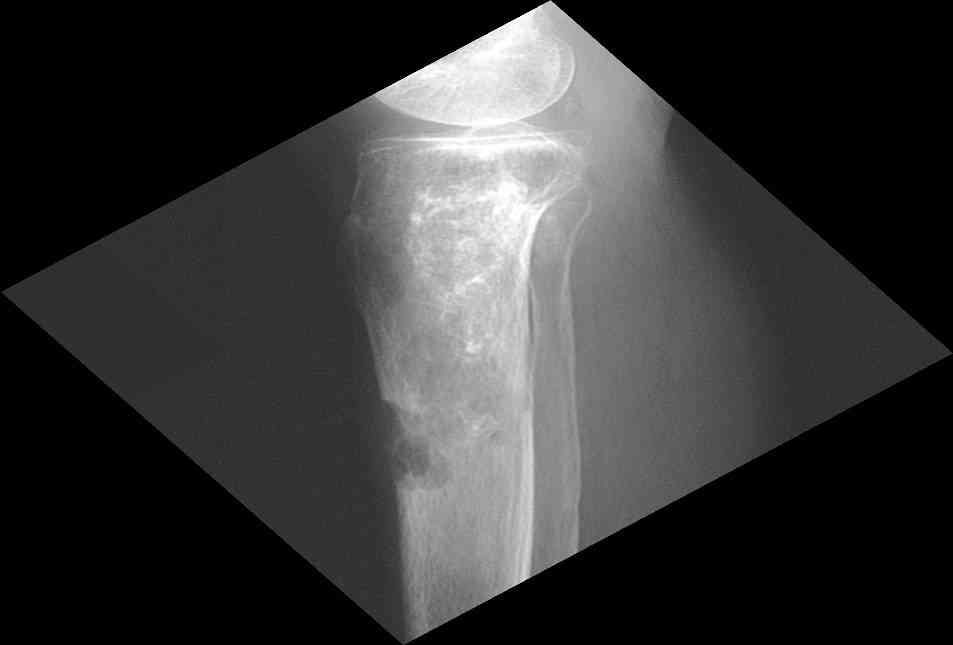

Изменения структуры костей у Вашего пациента больше похожи на

полиоссальную форму фиброзной дисплазии или болезнь Педжета, возможены

также инфаркты костного мозга б.берцовых костей. К сожалению, качество

снимка не очень хорошее, не понятно, сохранен ли кортикальный слой

б.берцовых костей по передней поверхности.

Для примера привожу случай из архива американской ассоциации

рентгенологов (ACR) - развитие злокачественной фиброзной гистиоцитомы

на левой б.берцовой кости у пациента с множественными инфарктами

костного мозга (рис 4,5 - левая, рис 6 - правая)